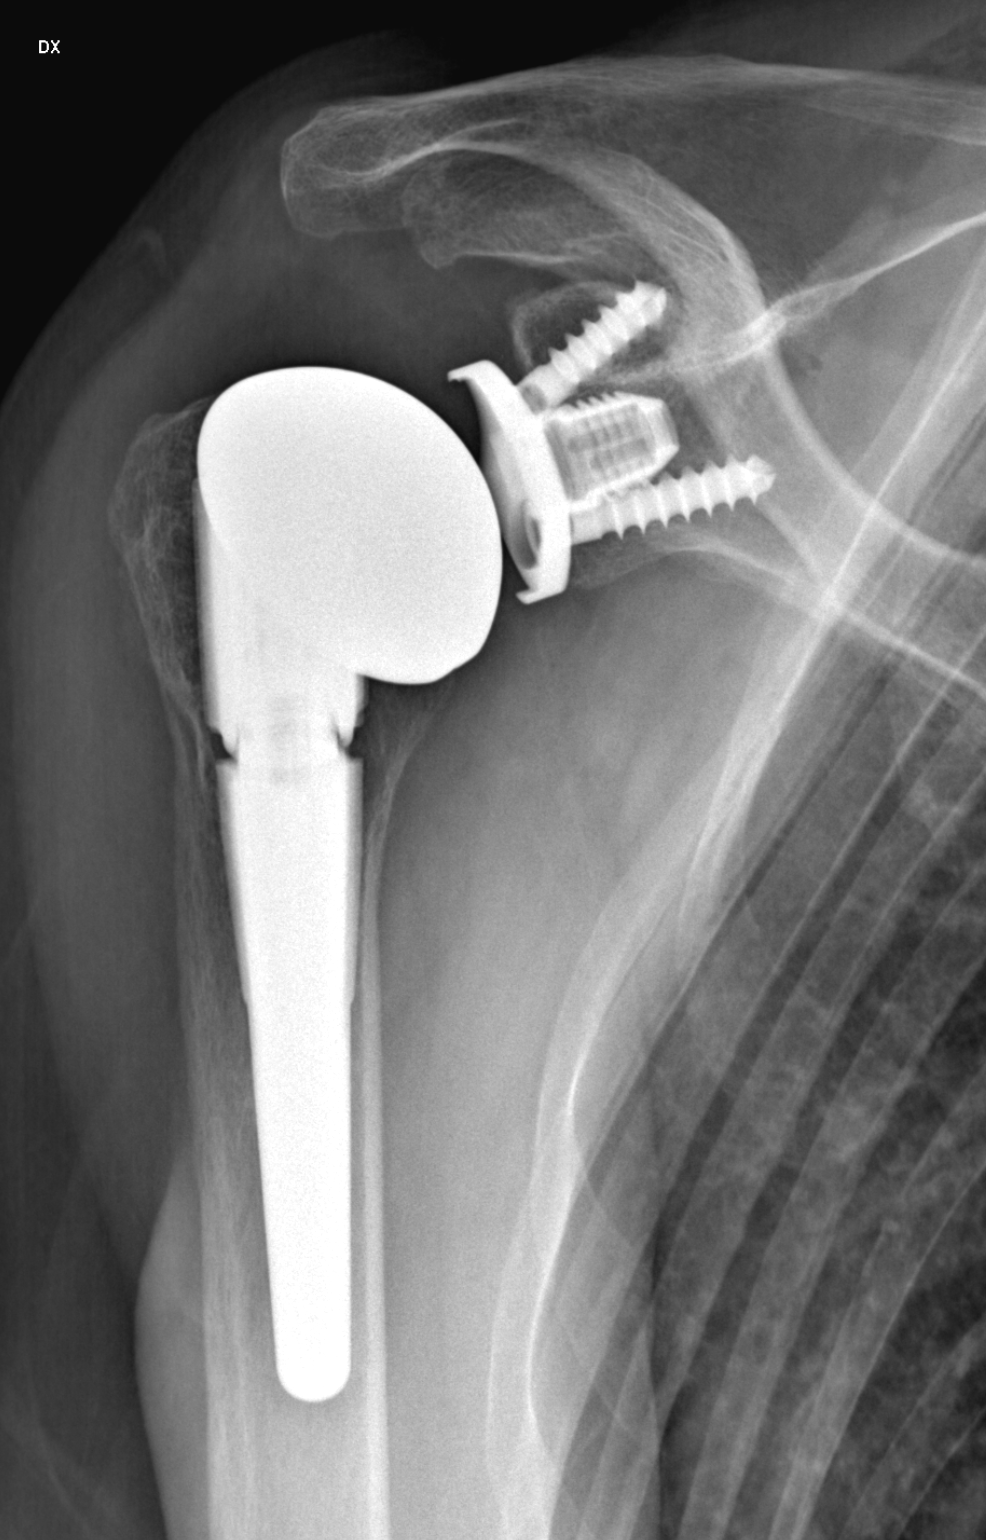

L’esame radiografico risulta indispensabile per verificare il corretto posizionamento delle protesi articolari (di spalla, di anca, di ginocchio, di gomito) e per monitorare nel tempo la loro condizione.

Presso lo STUDIO DI PIETTO è possibile eseguire esami radiologici ortopedici specialistici per la valutazione delle patologie articolari e della colonna vertebrale.